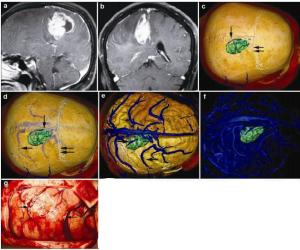

20170308100354  Figure 3 Magnetic resonance imaging, reconstruction images, and actual operative view in a 62-year-old female patient with a malignant meningioma in right frontal lobe. (a, b) T1 enhancement scans: The tumor presented as heterogeneous enhancement. (c) 3D reconstruction: The tumor located behind the coronary suture (horizontal double arrow) and adjacent to sagittal suture (vertical single arrow). (d) 3D reconstruction (skull semitransparent): This picture not only shows the relationship between tumor and sutures (coronary suture, horizontal double arrow; sagittal suture, vertical single arrow) but also shows the relationship between tumor and the superior cerebral veins (horizontal double arrow). (e) 3D reconstruction (do not show the skull): The tumor locates between two superior cerebral veins (horizontal single arrow). (f) 3D reconstruction: This picture only shows the tumor and veins. (g) Intraoperative situation: The intraoperative situation is consistent with 3D reconstruction images.